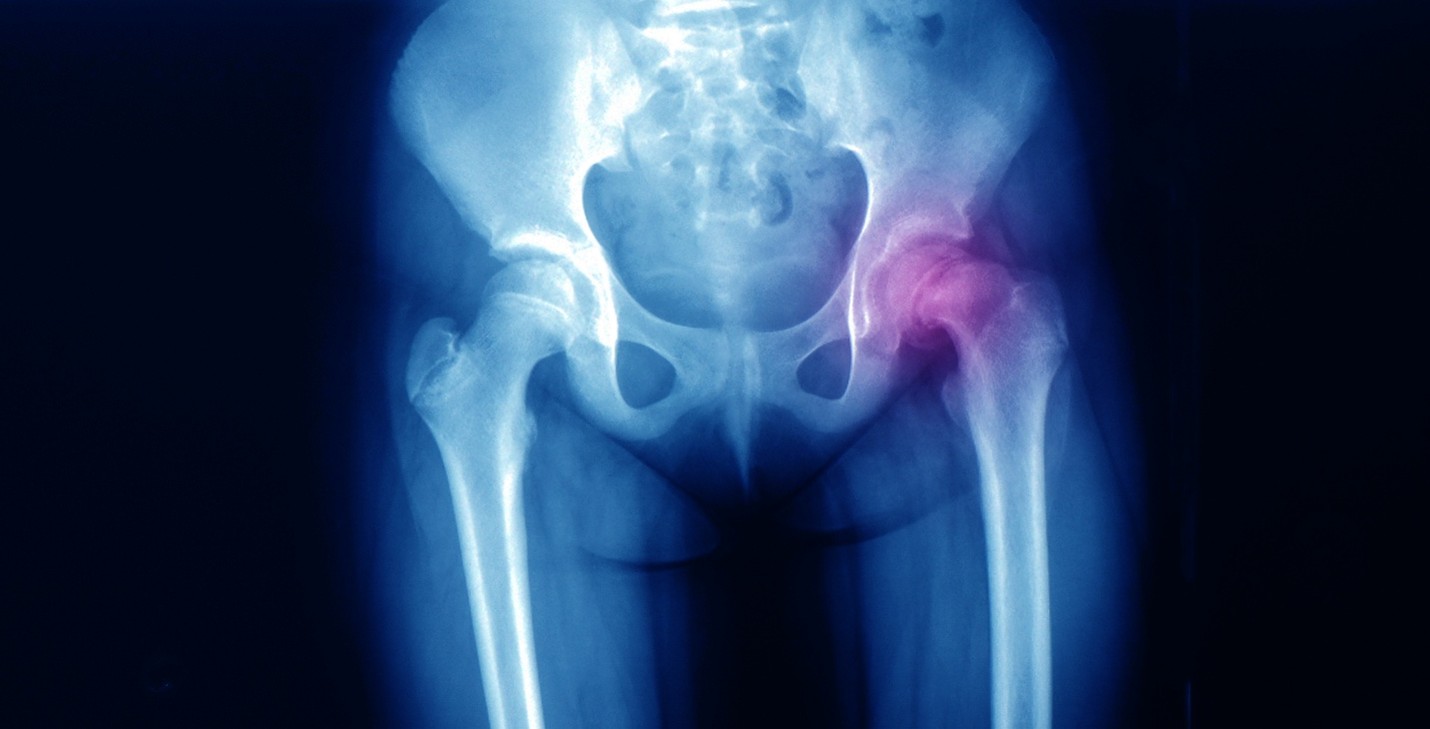

Slipped capital femoral epiphysis (SCFE) is a hip problem. It starts if the epiphysis (growing end) of the femur (thigh bone) slips from the ball of the hip joint. SCFE may develop in one or both legs.

Your child’s doctor will talk with you and your child about their symptoms. The doctor may watch your child’s gait (how they walk). Your doctor may order X-rays of your child’s pelvis and thigh.